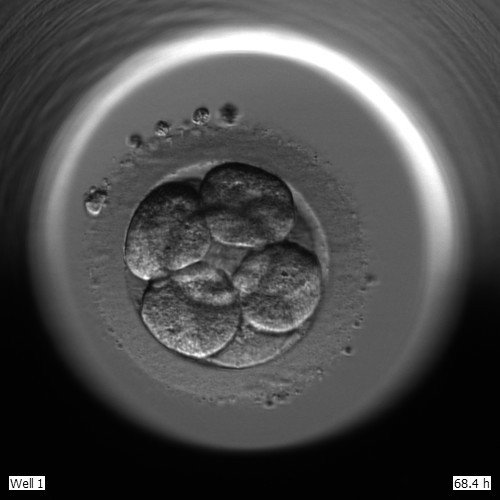

L’ovodonació, més enllà dels gàmetes 04/03/2017 Ins Josep Tapiró L’ovodonació, més enllà dels gàmetes Llegeix més »